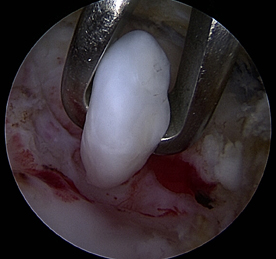

- Ablation d’un corps libre sous arthroscopie

L’arthroscopie du coude permet d’enlever les corps libres dans l’articulation et les ostéophytes qui viennent buter en avant et en arrière de l’humerus. Il est également possible de libérer les rétraction de la capsule articulaire pour améliorer la souplesse de l’articulation.